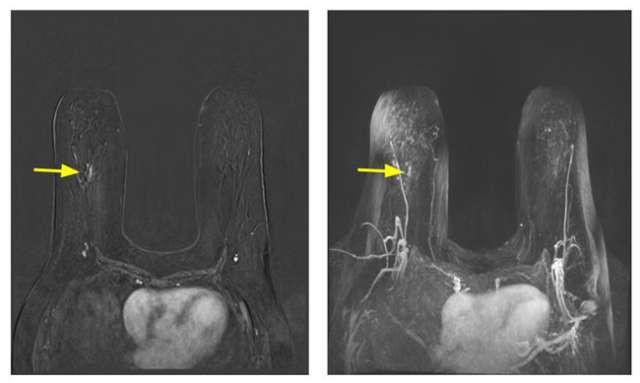

Contrast-enhanced breast MRI is more sensitive than mammography or ultrasound in high-risk populations. To this end, those considered to be high-risk, namely individuals with genetic mutations and their untested first-degree relatives, history of prior chest radiation, and calculated lifetime risk of 20% or more, are recommended to undergo contrast-enhanced breast MRI examination annually starting at the age of 25-30 years in addition to annual mammography. Supplemental ultrasound should replace MRI examination only in those who cannot tolerate MRI. Individuals with a history of breast cancer before age 50 or a personal history of breast cancer and dense breasts should also undergo an annual MRI examination and annual screening mammography. MRI examination can also be considered in individuals with a personal history of atypia or LCIS if additional risk factors exist. No specific recommendation for MRI screening exists for those individuals with dense breast tissue at this time. Annual MRI in high-risk populations is a complementary examination to mammography and should not replace it. Hence, screening MRI and mammography can be done concurrently or staggered by six months.